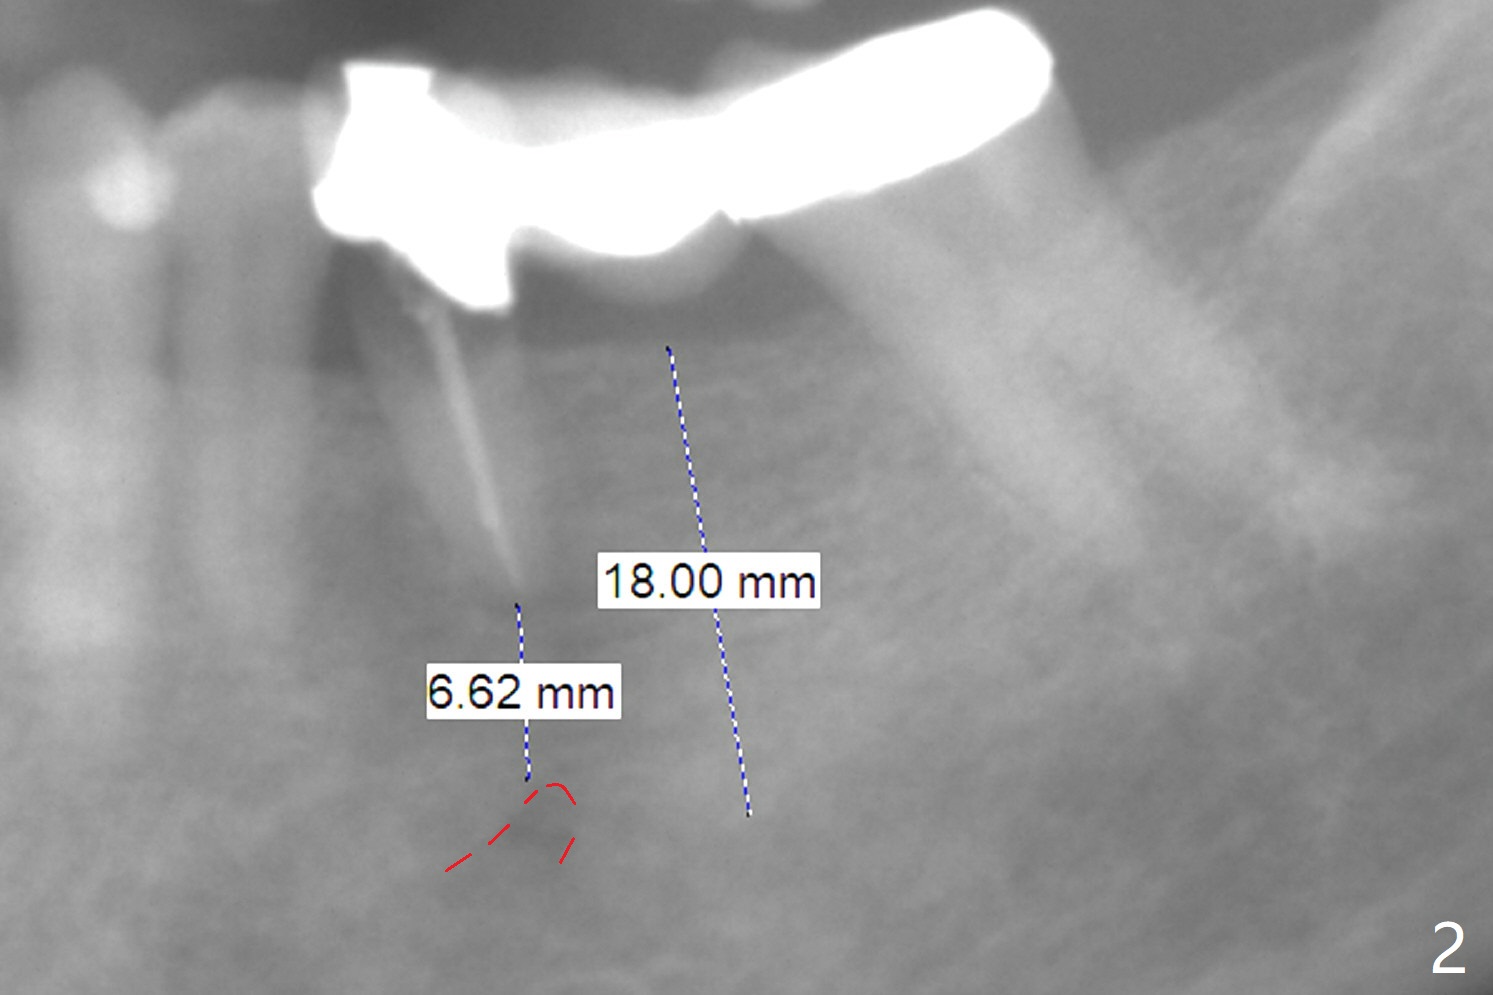

A 64-year-old woman has a lower left FPD (Fig.1) with the abutment at #20 having open margin (*). The tooth seems to be non-salvageable and to be replaced by an implant. There is ~ 6 mm native bone (Fig.2). Mesial osteotomy should be safer than orthodox one (Fig.3). To have the best reference, the FPD will be first sectioned between #19 and 20 (Fig.3 red line). Initial depth will be 18 mm (gingival level). An implant will be placed using the pontic at #19 and the tooth #21 for orientation guide. After placement of an abutment at #20 and use of gauze to seal the socket, the FPD will be sectioned between #18 and 19. It appears that the tooth #20 and probably #18 have fractured (Fig.4). Implants will be most likely placed at #18 and 20. The existing bridge will be used as a provisional.